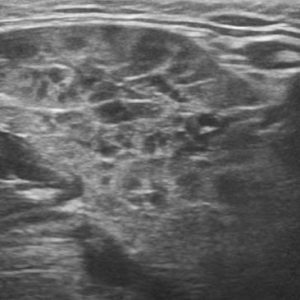

U tuyến nước bọt

Lượt xem: 170» 17-01-2021 -

U tuyến nước bọt

Lượt xem: 174» 17-01-2021 -

U tuyến nước bọt

Lượt xem: 149» 17-01-2021 -

U tuyến nước bọt

Lượt xem: 147» 17-01-2021 -

U tuyến nước bọt

Lượt xem: 146» 17-01-2021 -

U tuyến nước bọt

Lượt xem: 151» 17-01-2021 -

U tuyến nước bọt

Lượt xem: 146» 17-01-2021 -

U tuyến nước bọt

Lượt xem: 136» 17-01-2021 -

U tuyến nước bọt

Lượt xem: 132» 17-01-2021 -

U tuyến nước bọt

Lượt xem: 209» 17-01-2021 -

U tuyến nước bọt

Lượt xem: 150» 17-01-2021 -

U tuyến nước bọt

Lượt xem: 185» 17-01-2021 -

U tuyến nước bọt

Lượt xem: 151» 17-01-2021 -

U tuyến nước bọt

Lượt xem: 212» 17-01-2021 -